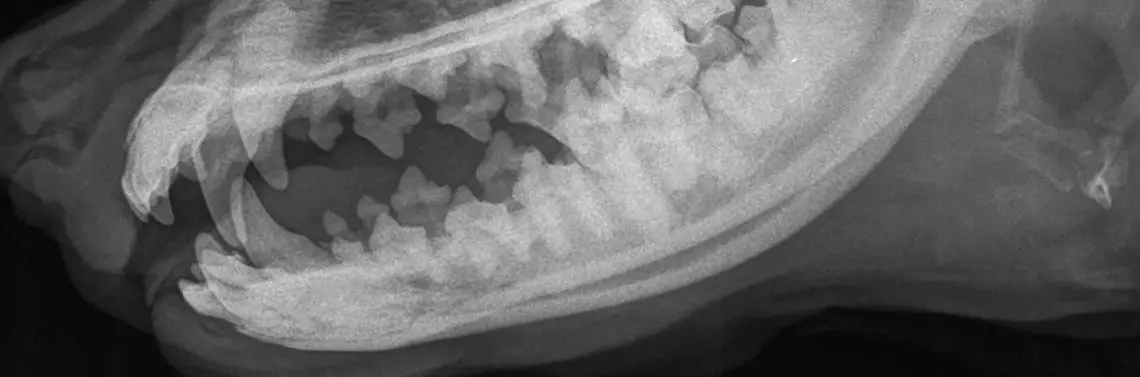

Około 10-letnia sterylizowana suczka rasy cocker spaniel trafiła do przychodni z niebolesną, fluktującą zmianą u podstawy ucha. W badaniu klinicznym nie stwierdzono odchyleń od normy, obwodowe węzły chłonne były niepowiększone, krtań niereaktywna, osłuchowo brak zmian, temperatura ciała również bez zmian. Po antybiotykoterapii (amoksycylina z kwasem klawulanowym w dawce 20 mg/kg dwa razy dziennie przez 10 dni) stan psa wracał do normy, jednak po kilku dniach od zakończenia terapii objawy nawracały. Z wywiadu wiadomo, że pies mógł spożywać kości lub patyki. Okolica zmiany była niebolesna, nie towarzyszył jej obrzęk. Pacjentka wykazywała niechęć do jedzenia. Podczas ba...